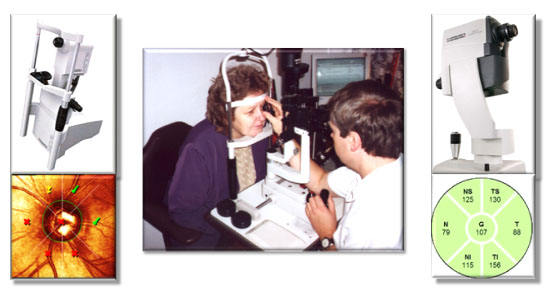

Heidelberský retinální tomograf považujeme stále jako hlavní zobrazovací metodu v diagnostice glaukomové neuropatie.

HRT3 používá tyto analýzy:

* MRA - Moorfieldská regresní analýza

* GPS - Glaukomové pravděpodobnostní skóre

* TCA - Topografická analýza změn v čase

SOCT Spectralis nám umožnuje tyto glaukomové skeny:

* BMO-MRWW - měření minimální tloušťky neuroretinálního lemu od okraje Bruchovy membrány

* RNFL - měření tloušťky vrstvy nervových vláken v okolí zrakového nervu

* PPAA - analýza asymetrie vrtsvy sítnice v centrální krajině

* GCL - analýza vrstvy gangliových buněk v centrální krajině

* MULTICOLOR - barevný snímek zrakového nervu a jeho okolí dokumetující případné výpadky ve vrstvě nervových vláken

Oční tomografy HRT3 a SOCT jsou základními vyšetřeními při komplexním vyšetření. Přesto je velmi důležité vždy se také podívat Volkovou čočkou 60D nebo 90D v mydriáze na štěrbninové lampě a zhodnotit " vlastním pohledem" papilu a vrstvu nervových vláken /v zeleném světle/. Potom teprve popsat nálezy na tomografech.

Použití obou očních tomografů HRT3 a SOCT nám dává větší diagnostickou jistotu, neboť se v naší dlouholeté praxi setkáváme, že nález určité typy glaukomové neuropetie, projeví jen na jednoz nic a na druhém nikoliv a naopak.